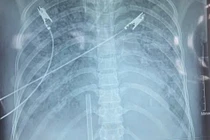

Bệnh nhân nhập viện trong tình trạng sốt, sốc nhiễm khuẩn, nhiễm khuẩn huyết, thở oxy gọng kính, áp xe đa ổ đa tạng...

Thủy đậu là bệnh lành tính nhưng người bệnh rơi vào nguy kịch rất nhanh khi xảy ra biến chứng viêm phổi, viêm não, nhiễm trùng da hoặc bội nhiễm vi khuẩn…